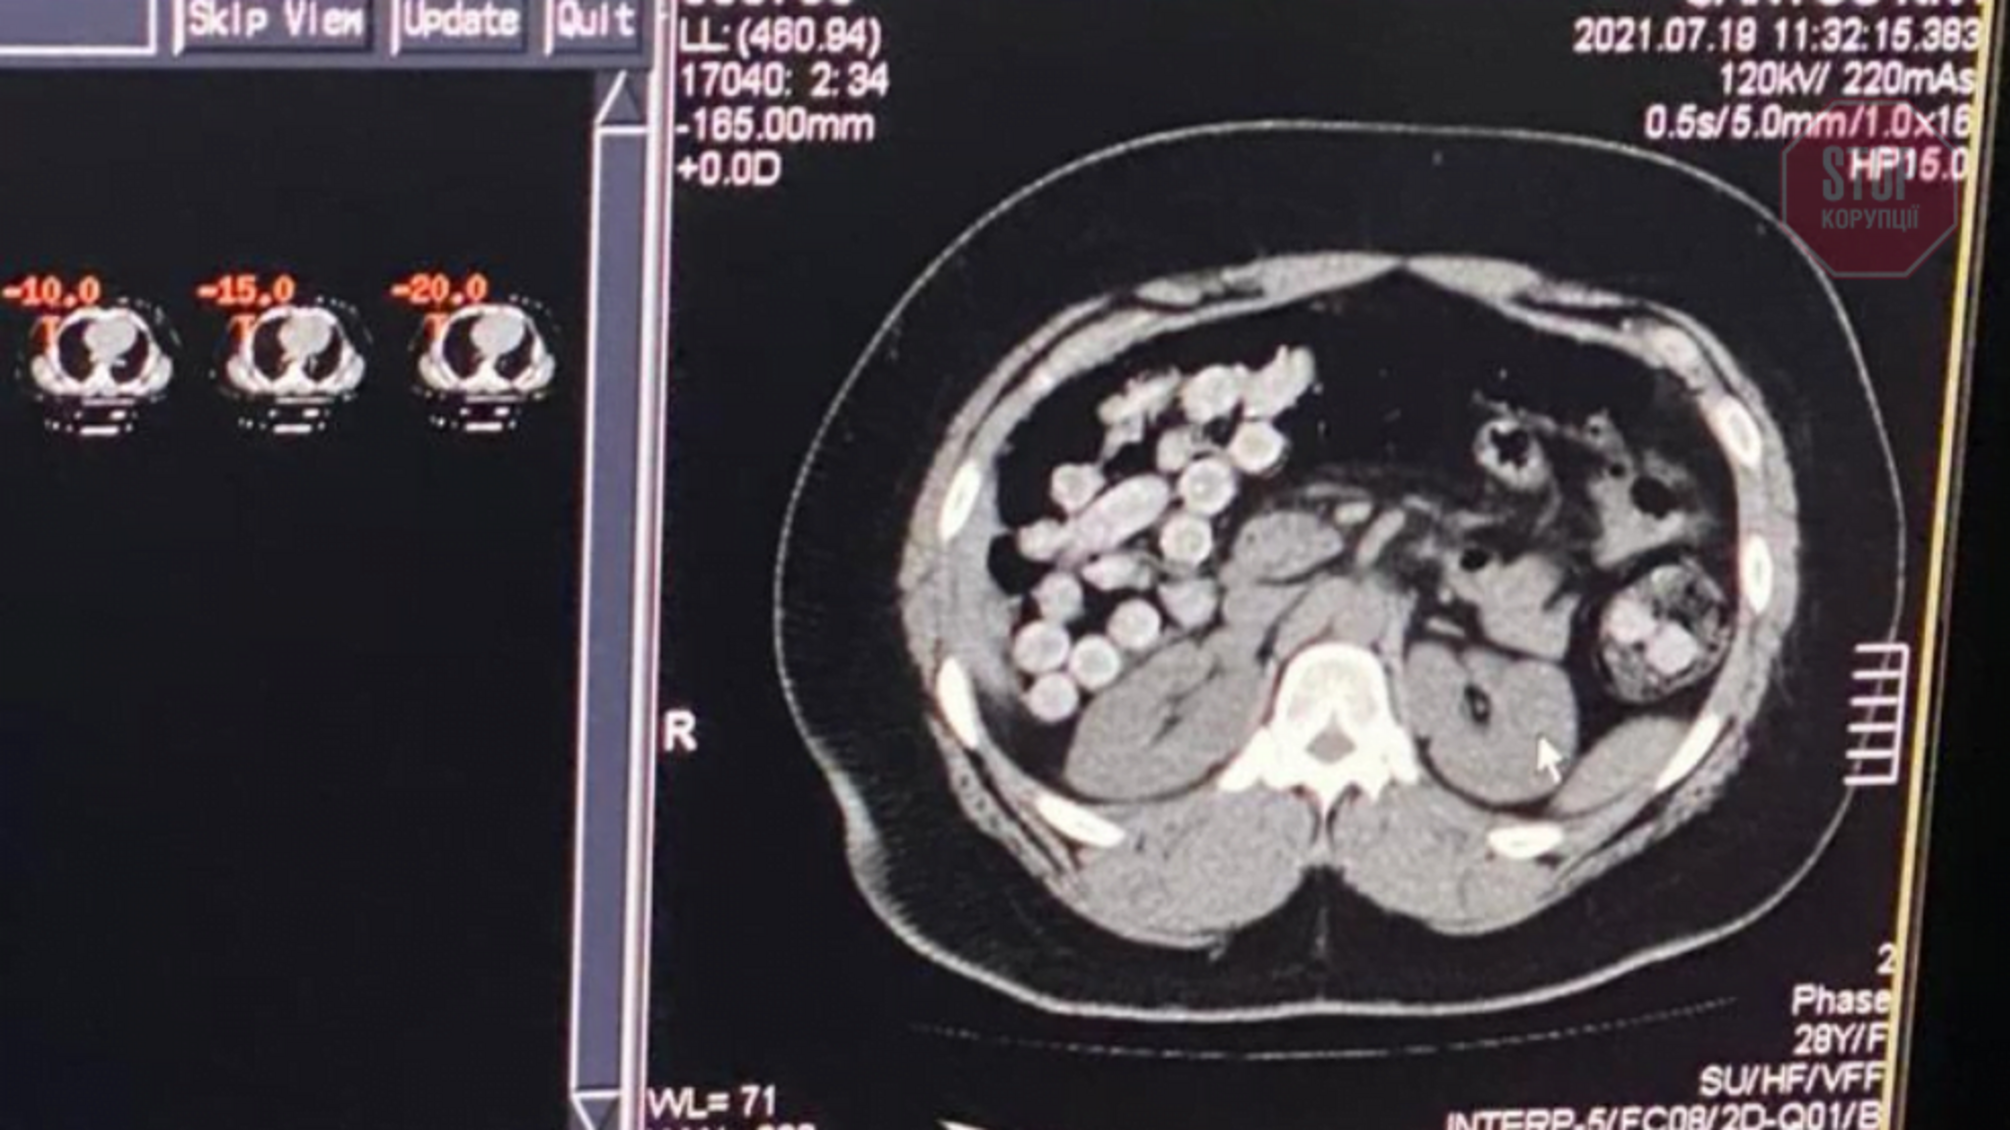

У відомстві зазначили, що один з наркокур'єрів переміщував наркотики в особистих речах. Інший намагався перевезти через державний кордон понад 1 кг кокаїну в шлунково-кишковому тракті, передає "РБК-Україна".